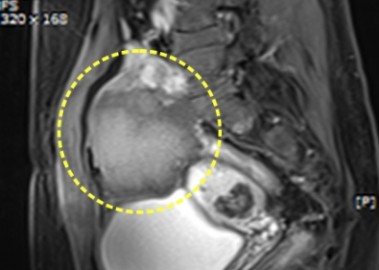

거대 자궁선근증 치료 사례